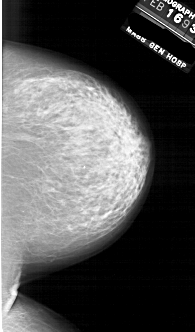

A_1854_1.RIGHT_CC

RIGHT_CC LINES 6301 PIXELS_PER_LINE 3691 BITS_PER_PIXEL 12 RESOLUTION 43.5 NON_OVERLAY